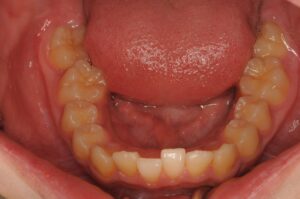

下の歯の噛む面から観た写真